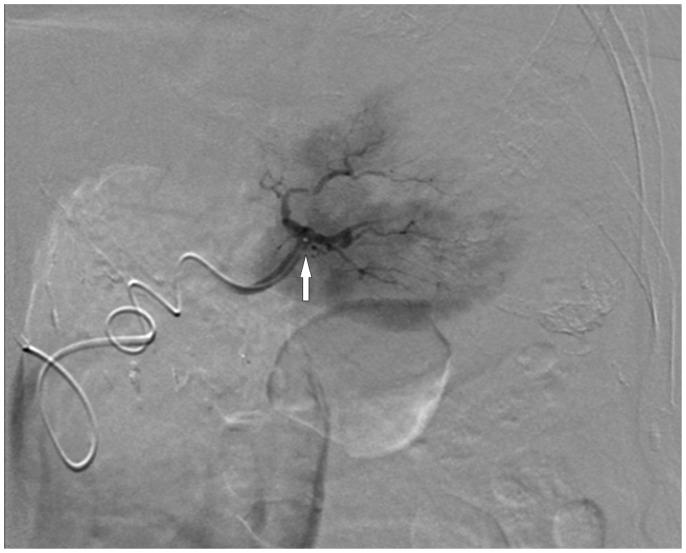

Splenic injury is a rare complication following colonoscopy with fewer than 100 reported cases worldwide to date. We describe a case of splenic laceration presenting 5 days following diagnostic colonoscopy. Although hemodynamically stable, active contrast extravasation on contrast-enhanced multidetector computed tomography predicted likely failure of conservative management. Splenic artery angiography confirmed active extravasation from the lower splenic pole and the patient was successfully treated with super selective coil embolization of a lower pole splenic artery branch. This is the eighth reported case of endovascular treatment of splenic injury following colonoscopy. To our knowledge, however, superselective splenic artery embolization has not been previously reported to treat this rare endoscopic complication.